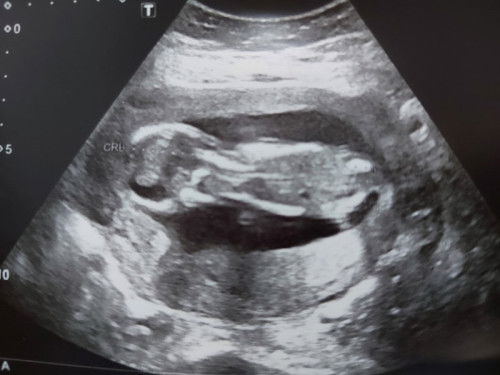

ดิฉันเป็นคุณแม่อายุ41ปี ที่อยากมีลูกมาก เมื่อได้ข่าวดีก็ดูแลประคบประหงมลูกน้อยอย่างดี แต่ด้วยว่าแม่ยังทำงานจึงต้องเดินเยอะ แต่ก็ไม่เท่ากับที่เดินขึ้นลงบันได4ชั้น และผลคือเลือดออกบริเวณข้างรกและทำให้รกที่เกาะผนังมดลูกไม่แข็งแรง และทำให้มีเลือดออกทางช่องคลอด จึงนอนรพ.นิ่ง กินนอนถ่ายบนที่นอนตั้งแต่11-18พ.ค.66 เช้า เลือดหยุดไหล กลับบ้านได้ แต่แล้วในคืนนั้นเอง ตอนตี3เริ่มปวดท้องบีบมดลูกเป็นระยะๆ ตอนตี4เริ่มมีเลือดออก ตอนตี5น้ำเดินจึงไปรพ. ปวดเบ่งและคลอดลูกออกมาตอน7.30น. ได้เห็นหน้าลูกลูกมีแขนขายาวจมูกโด่งมีทุกอย่างครบ แต่ไม่มีลมหายใจ #ลูกจากแม่ไปแล้ว วันนี้ผ่านไปแล้ว5วัน แม่คิดถึงลูกเหลือเกิน หากอายุครรภ์มากกว่านี้อีกสักนิดลูกคงสามารถมีชีวิตอยู่ได้ #อยากทราบว่าหากคลอดก่อนกำหนดอายุครรภ์สักกี่เดือนจึงจะสามารถมีชีวิตอยู่ได้คะ #ขอคำแนะนำหน่อยค่ะ